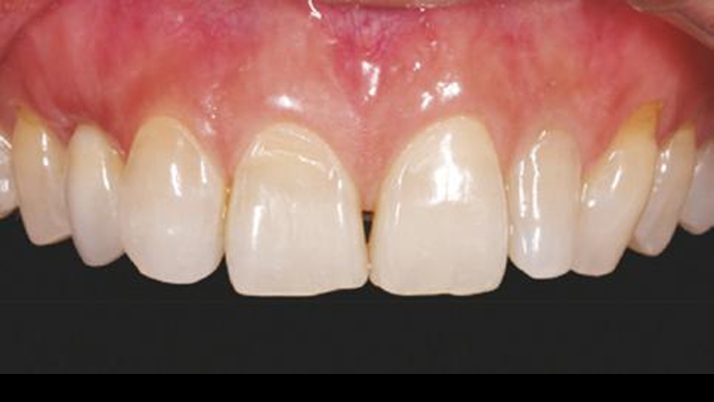

Clinical case: Patient-centered approach: treatment strategy for Root Membrane Technique & delayed implant placement

- Courtesy of Dr. Yoshiharu Hayashi, Japan -

“Advanced IntermezzoTM – one-piece solution for immediate placement & esthetic result in anterior region or narrow space.”